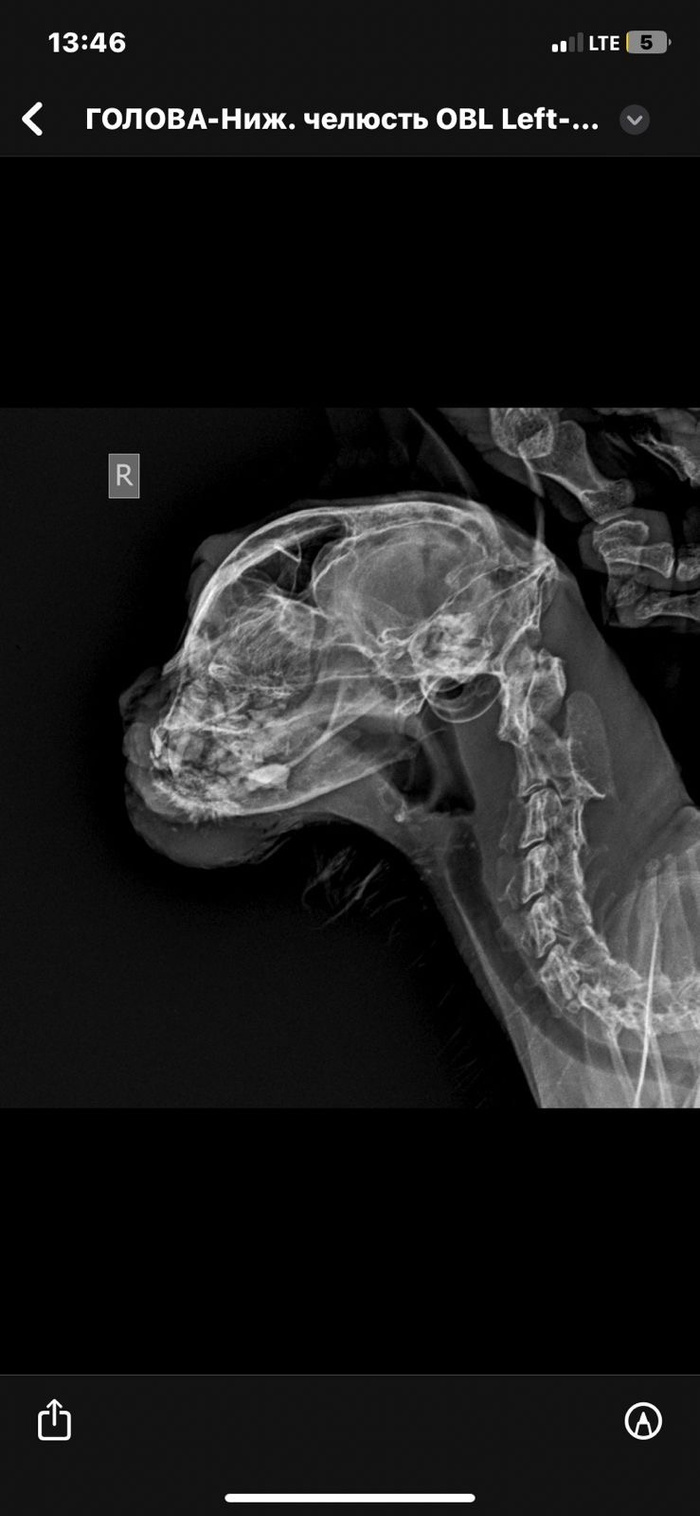

Здравствуйте, коту 18 лет, кастрирован, зубов почти нет, вес 2.7кг

Очень быстро вздулся подбородок и прорвался, оттуда сочится жидкость.

Сделали рентген, сказали ВОЗМОЖНО онкология, послали на кт под наркозом, мы соответственно не сделали из-за возраста.